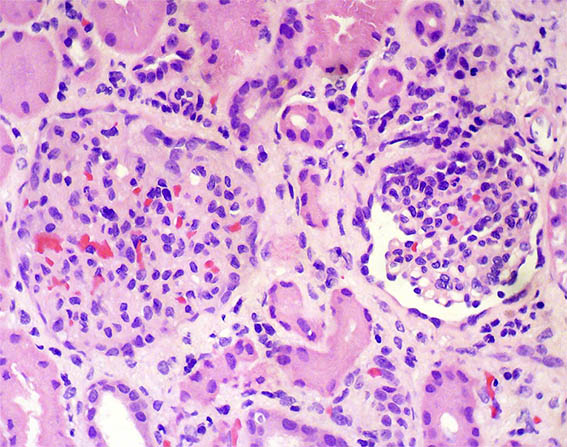

Con diagnóstico de síndrome nefrótico, se hace biopsia renal. Observe las imágenes.

Figura 4. H&E, X400.